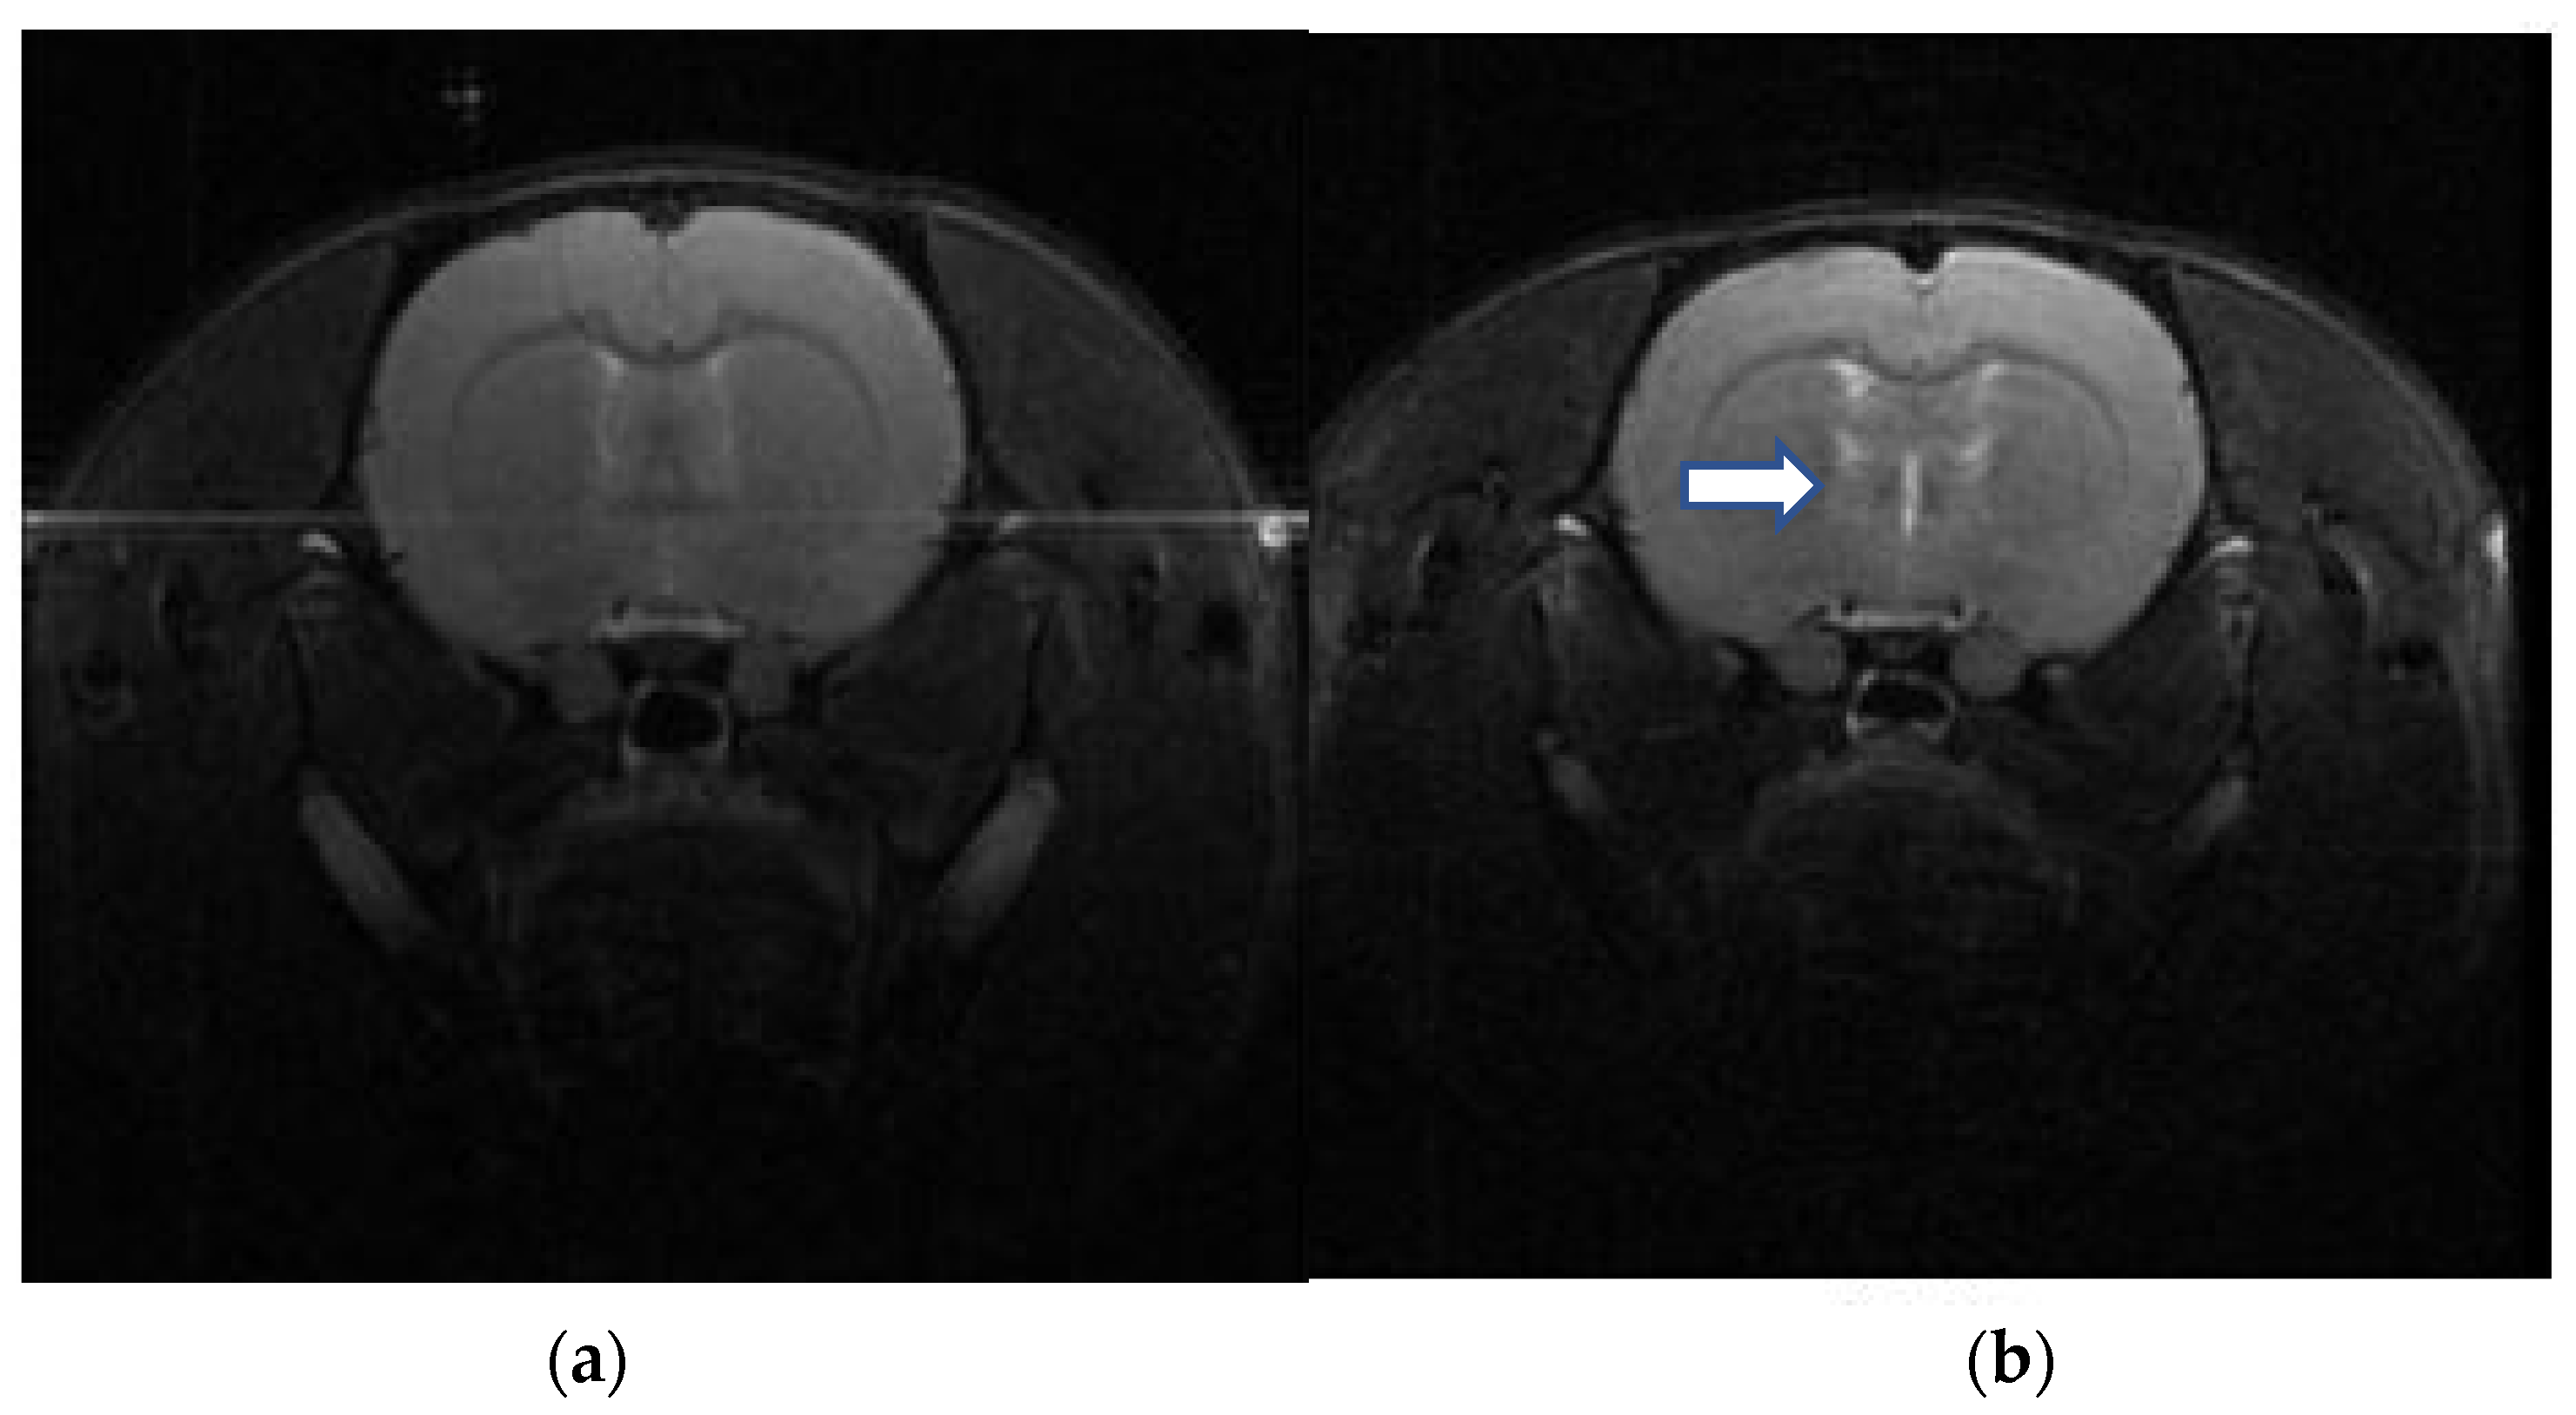

4.1. Imaging Study for DAI

Regions identifiable by T2-weighted contrast are depicted in Figure 3. The elevated signal intensity changes in the subcortical and deep brain tissues indicate DAI following a 3.8 kg•m/s impulse over 15 s, compared to a normal rat brain MRI.

Figure 3.

Brain MRI following modeling of a diffuse axonal injury (DAI). T2-weighted contrast MRI images display distinguishable regions. High signal intensity changes in the subcortical and deep brain tissues (white arrow) indicate the presence of DAI. (a) Normal rat brain MRI, (b) DAI rat brain MRI.

DAI often lacks clear radiological changes, even in cases with prominent neurological impairment [24]. MRI can evaluate DAI in patients with non-hemorrhagic lesions who show normal findings on CT scans. In the MRI images of patients with DAI, gliosis is observed as increased T2 signals may appear in areas susceptible to shearing injury, such as the grey–white matter junction, corpus callosum, and brainstem [25]. Several rodent models of TBI share similar imaging properties with human DAI [26,27], and there have been reports that MRI is effective in evaluating the appropriateness of DAI rat models [28]. In our study, gliotic changes were observed in the grey–white matter junction and deep brain tissue on brain MRI taken after DAI modeling, confirming the appropriateness of the modeling.